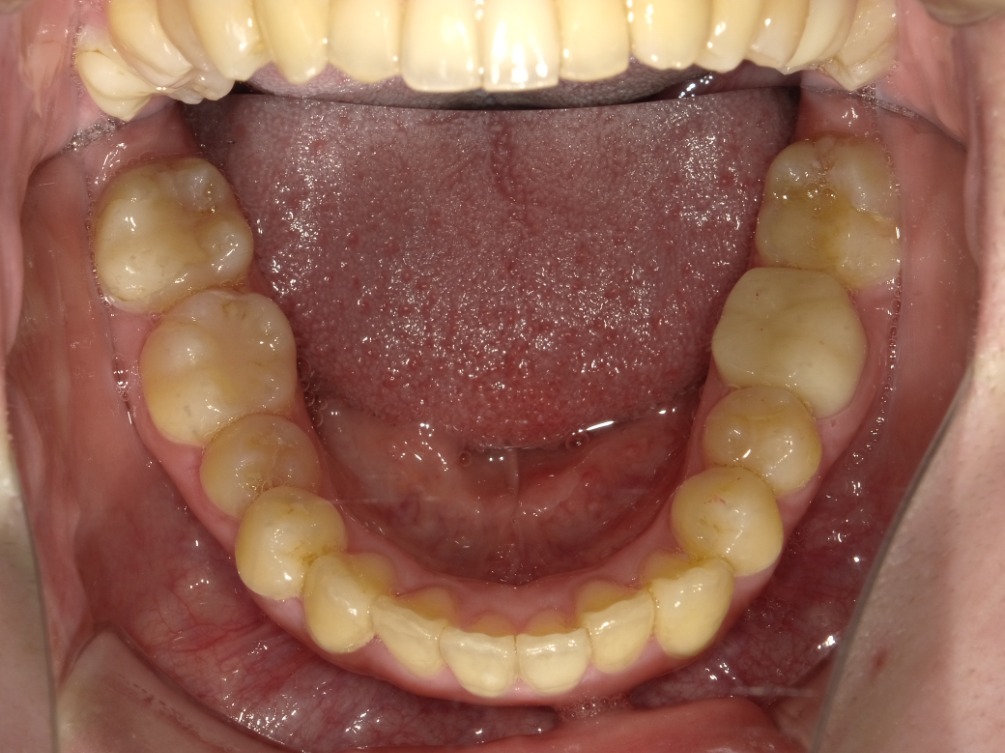

下顎

| 治療内容 | インビザライン 全顎〈抜歯あり〉 |

| 治療詳細 | 叢生や交叉咬合を整えるために、歯の表面にアタッチメント(白い突起)をつけ、IPR(歯と歯の間を削る)を行いました。 また、顎間ゴムと呼ばれる引っ掛けるゴムの補助装置も用いて治療を行いました。 抜歯を1本して治療を行いました。該当部分は義歯を使用しています。 |

| 患者情報 | 20代 女性 デンタルモニタリング使用 |

| 主訴 | 歯のがたつき 一部分だけかみ合わせが反対 |